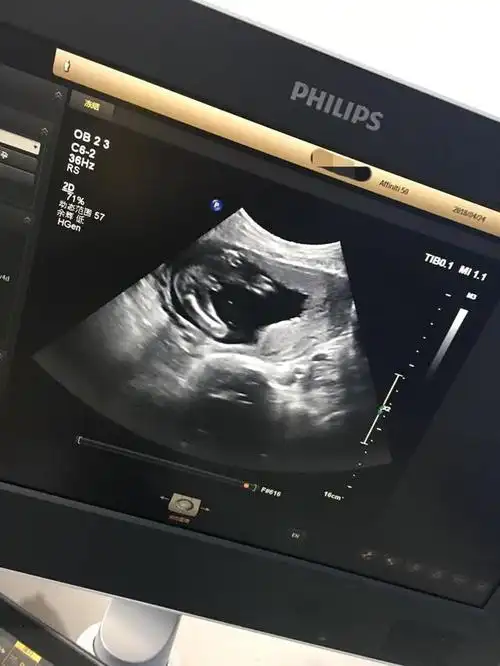

宝妈,看看我这个是男孩女孩啊!感觉是两个亮点,又像是三条线

求问我这三条线是肯定女宝了吗?

孕12周nt检查显示有三个亮点是男孩还是女孩

而三条线则是明显的女宝,如果没有看到明 显的三条线,就看两腿之间有

怀男孩b超有这些标志